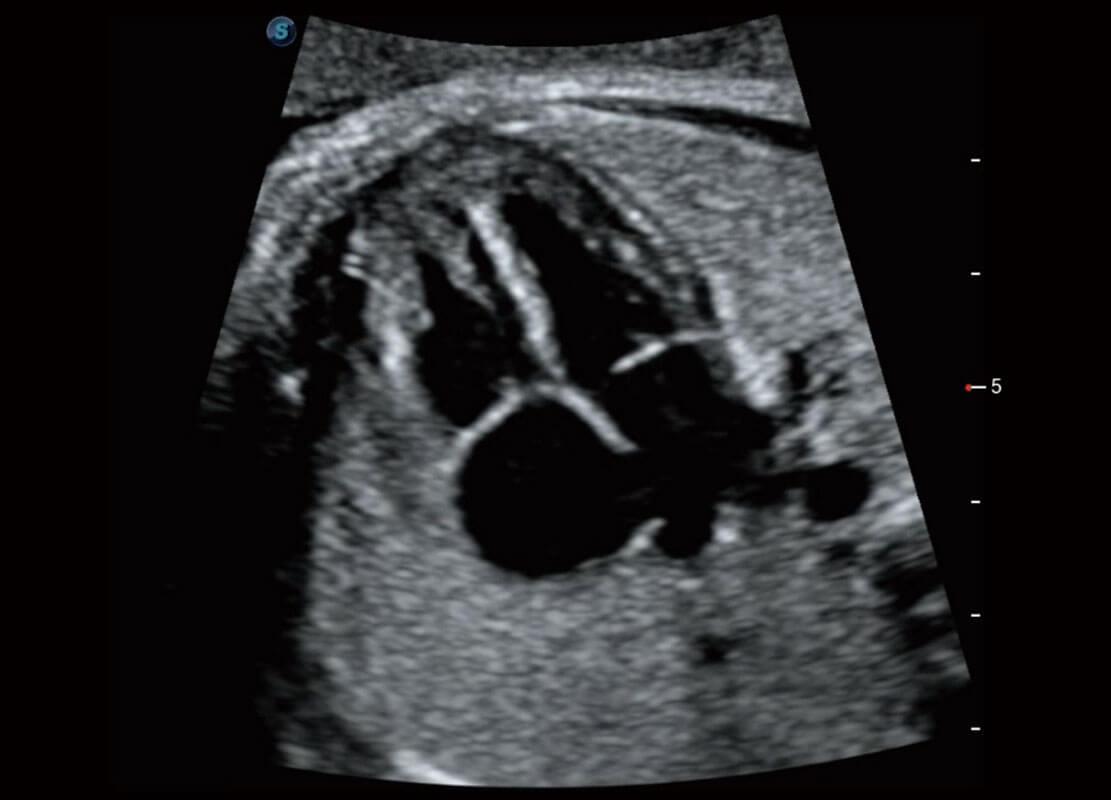

P60在胎儿早孕期超声筛查中为您带来优异的图像质量。

早孕-胎心